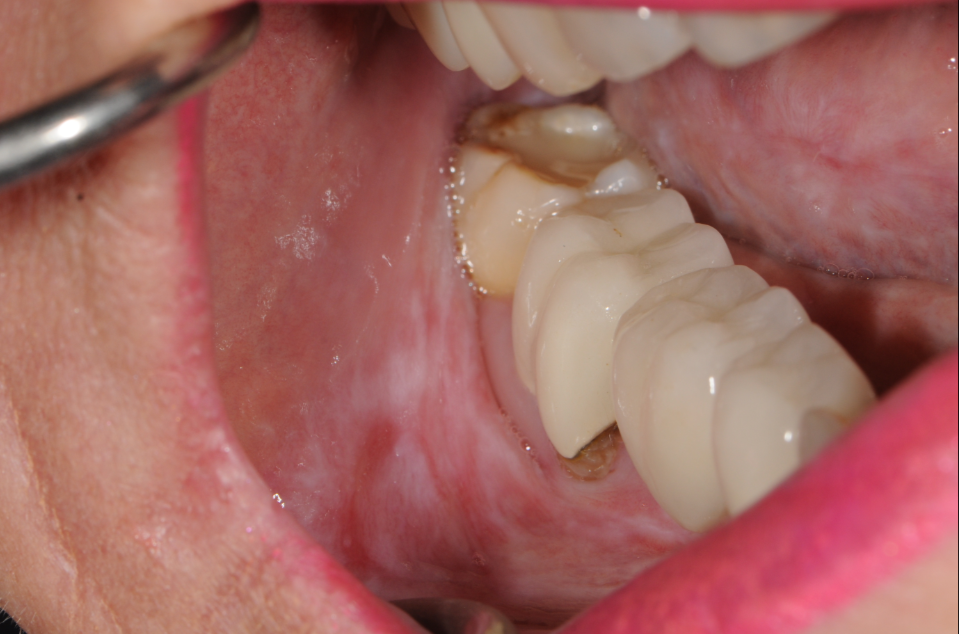

Clinical photo of oral lichen planus showing characteristic white, lacy striations (Wickham’s striae) on the inner cheek. Common presentation of chronic inflammatory oral mucosal disease. Useful for identifying symptoms of oral lichen planus in dental and medical diagnostics. CJ Henley, DMD, PA – Jacksonville, FL – for educational purposes on oral lichen planus diagnosis and treatment.

Oral lichen planus is a chronic inflammatory condition that affects the soft tissues inside the mouth. It often appears as white, lacy patches or red, swollen areas, and can cause burning or discomfort, especially when eating spicy or acidic foods. While not contagious or cancerous, it requires proper diagnosis and regular monitoring. At CJ Henley, DMD, PA in Jacksonville, FL, we offer personalized treatment for oral lichen planus to help manage symptoms and protect your oral health.

Description text goes hereWhite, lacy patches inside the cheeks or on the tongue

Red, swollen tissues